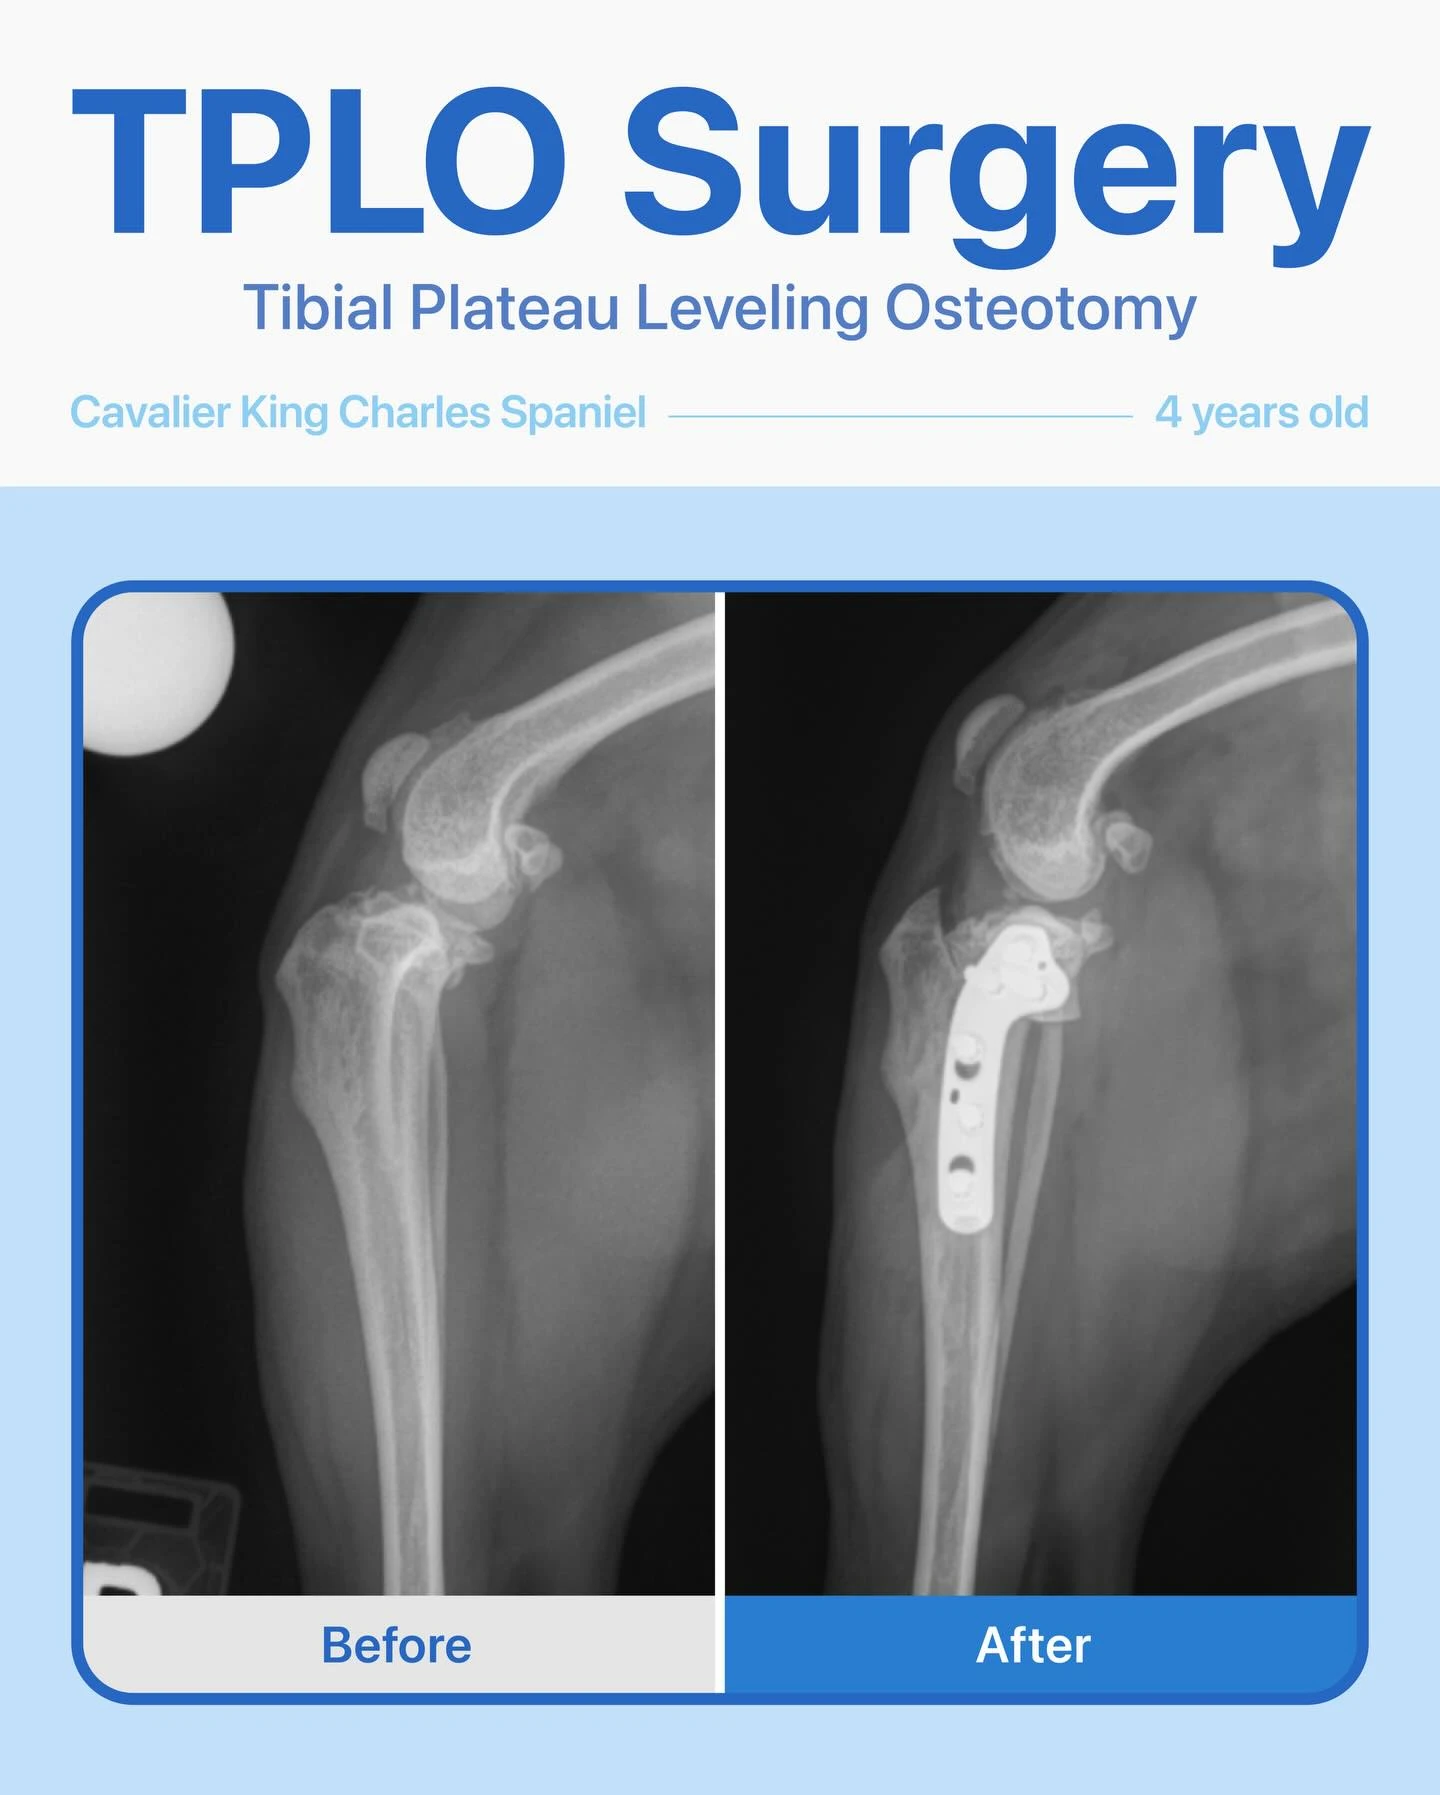

TPLO – Cavalier

This sweet 4-year-old female Cavalier King Charles Spaniel had been limping on her right back leg for about a year. Her owner noticed the leg looked thinner than the other and that she would yelp when we touched near her hip.

After radiographs, we confirmed a cruciate ligament tear, and she underwent a TPLO surgery.

The surgery went smoothly, and she’s healing wonderfully! We’re so … Read moreTPLO – Cavalier